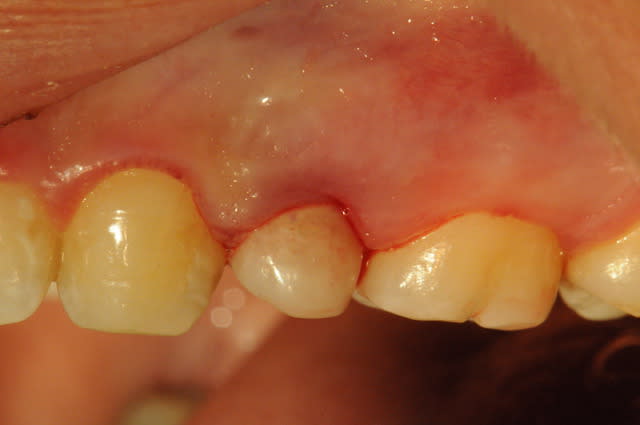

comme ça la prothèse conventionelle est zolie...

mis à part le liseret gris du collet suis content du résultat et pourtant c'était pas gagné d'avance : pas de GA ou peu et nécessité de faire une rog

donc la EII et ROG (nanobone + collagene +prf)

pas de MCI

à la réouverture déplacement en vestibulaire de la GA palatine pour redonner du "volume"

fouilla content il en faut peu pour être heureux..